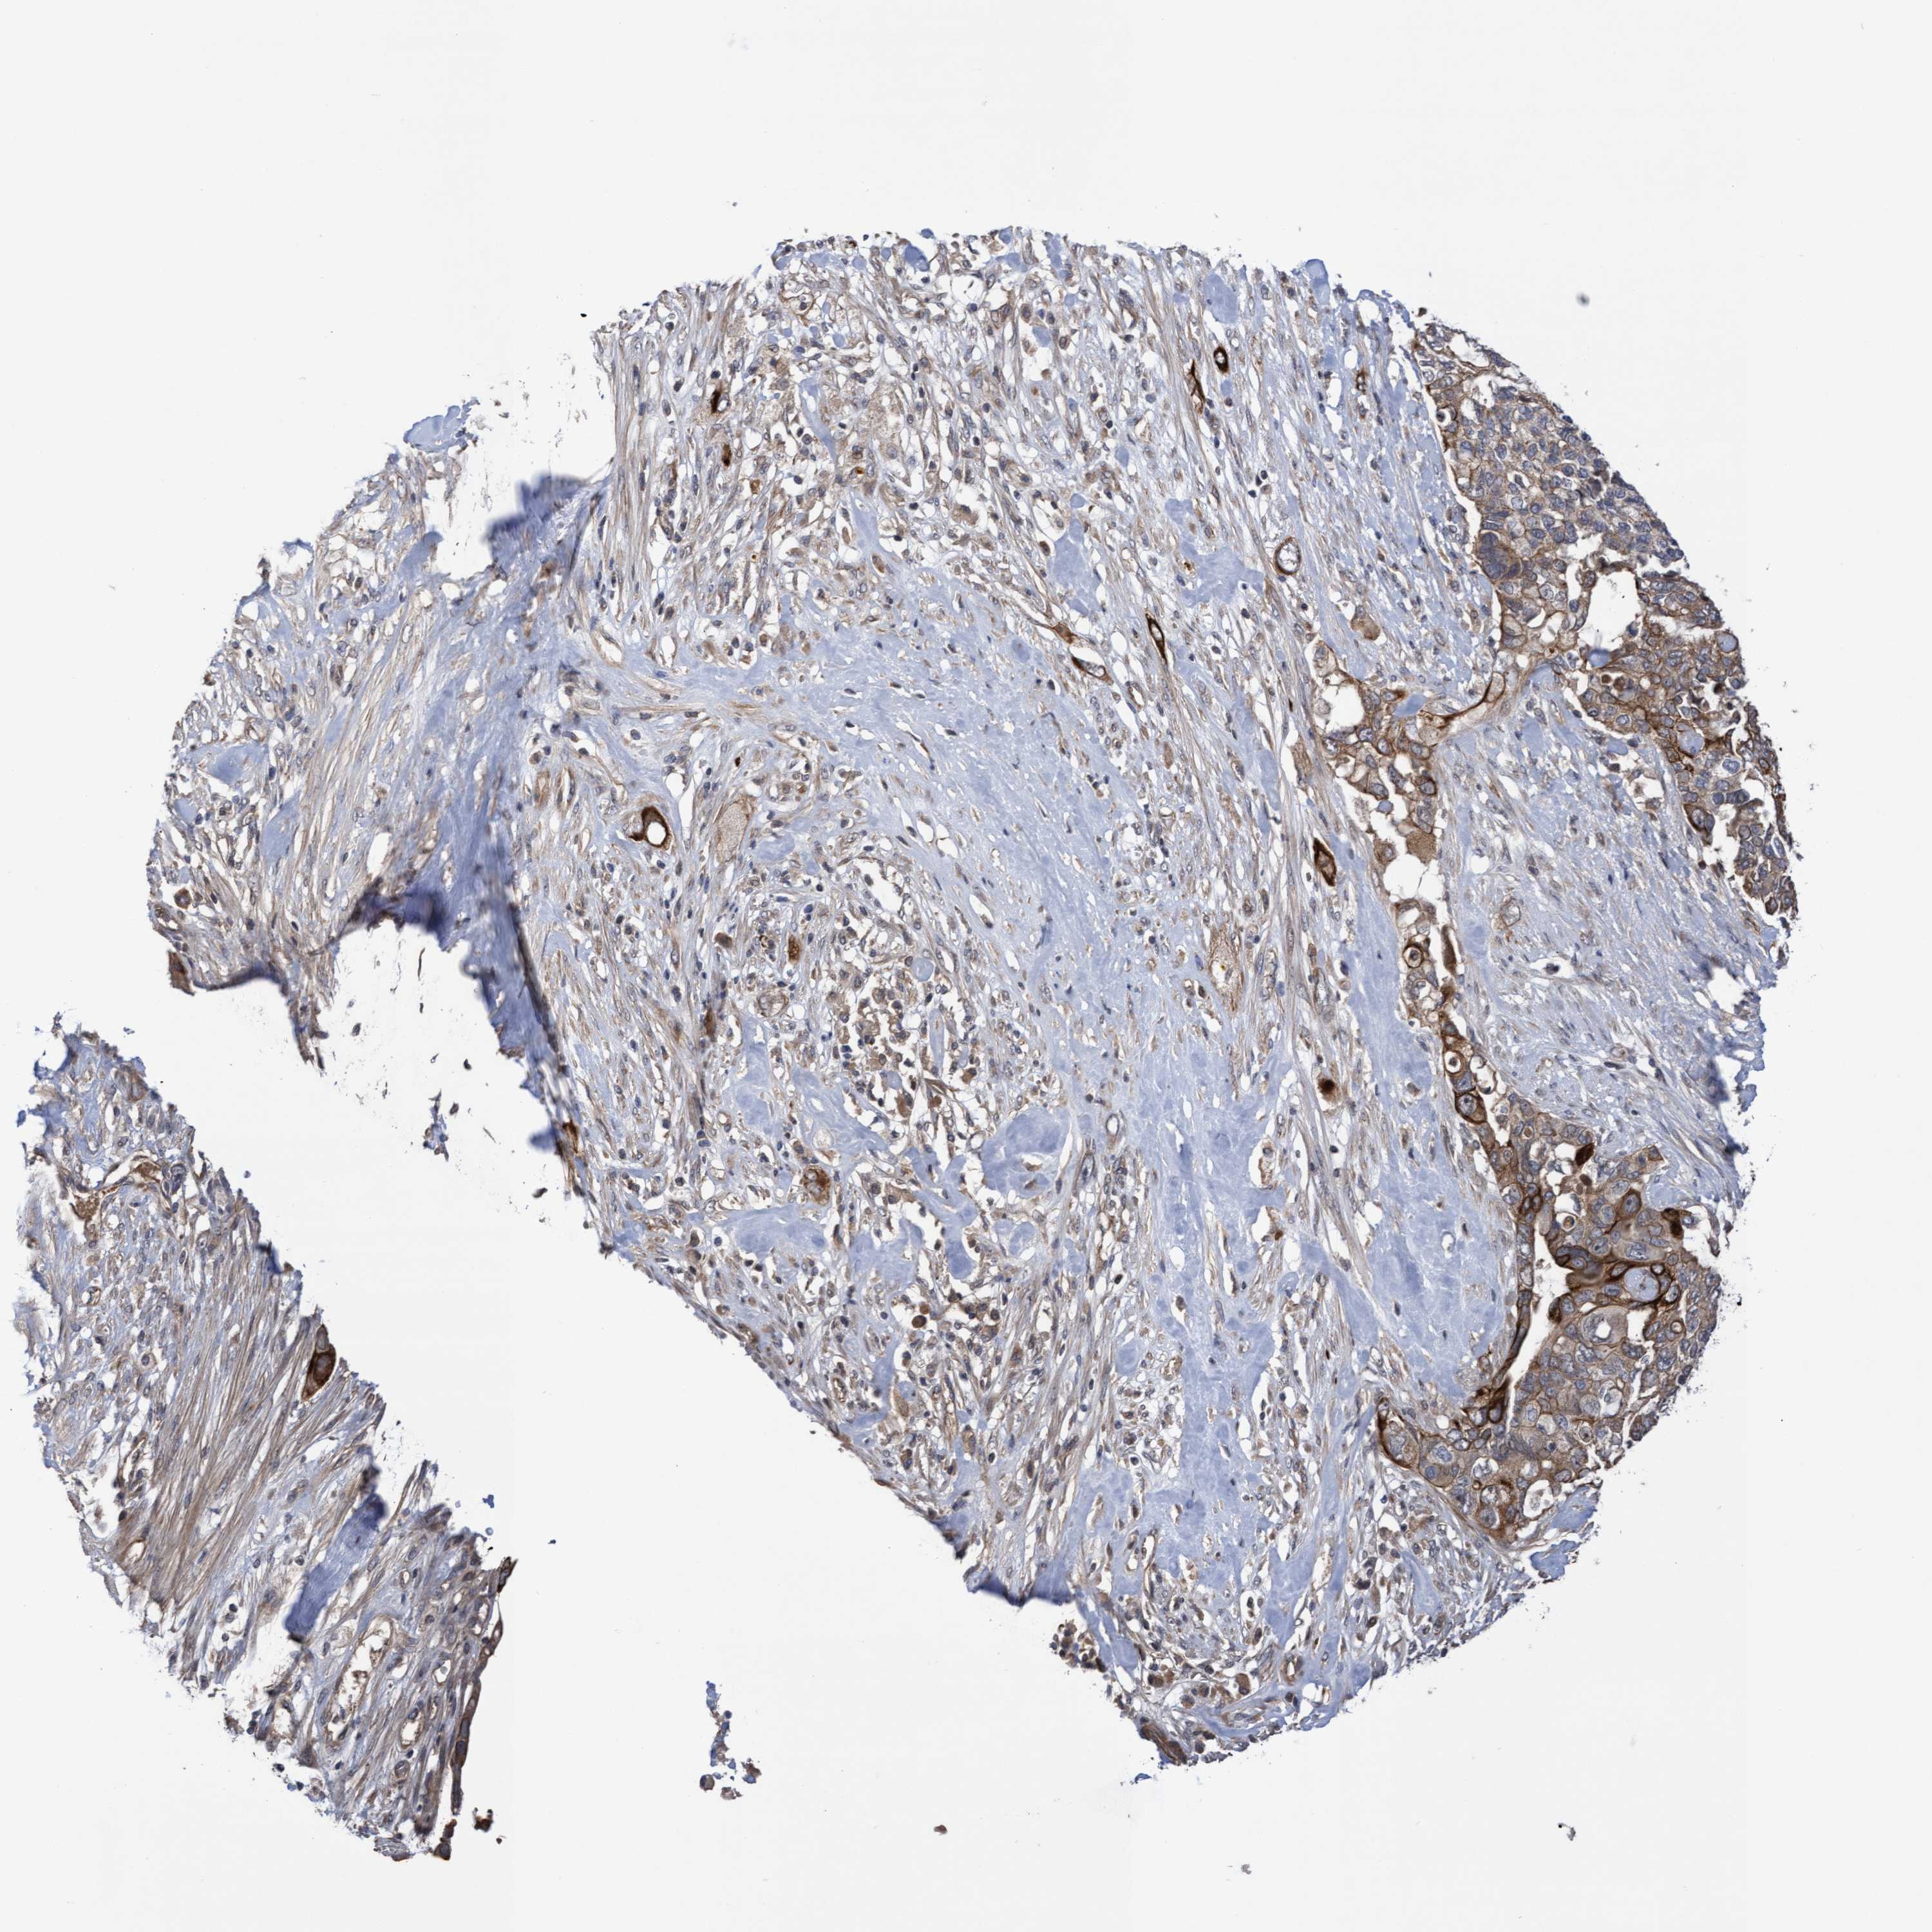

PANCREATIC CANCER - Protein expressioni

A mouse-over function shows sample information and annotation data. Click on an image to view it in a full screen mode. Samples can be filtered based on level of antibody staining by selecting one or several of the following categories: high, medium, low and not detected. The assay and annotation is described here.

Note that samples used for immunohistochemistry by the Human Protein Atlas do not correspond to samples in the TCGA dataset.

Antibody stainingi

Antibody staining in the annotated cell types in the current human tissue is reported as not detected, low, medium, or high, based on conventional immunohistochemistry profiling in selected tissues. This score is based on the combination of the staining intensity and fraction of stained cells.

Each image is clickable and will lead to virtual microscopy that enables deeper exploration of all samples and also displays staining intensity scores, fraction scores and subcellular localization as well as patient and tissue information for each sample.

Antibody HPA019033

Antibody HPA019167

Staining

High

Medium

Low

Not detected

Intensity

Strong

Moderate

Weak

Negative

Quantity

>75%

75%-25%

<25%

None

Location

Nuclear

Cytoplasmic/membranous

Cytoplasmic/membranous,nuclear

Adenocarcinoma, NOS